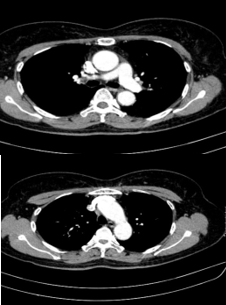

– Cắt lớp vi tính ổ bụng:

Hình 4: Hình ảnh cắt lớp vi tính ổ bụng có tiêm: chưa phát hiện tổn thương nghi ngờ thứ phát

– Cắt lớp vi tính ổ bụng: Không phát hiện tổn thương bất thường.